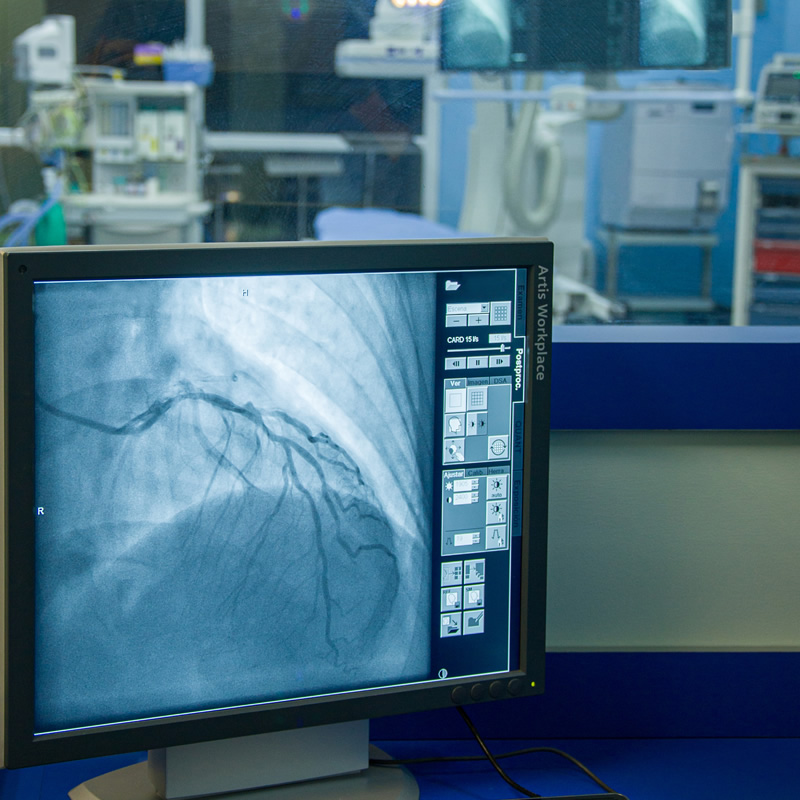

Sala Híbrida Quirúrgica (Quirófano / Cateterismo)

Procedimientos Endovasculares: Nuestra moderna Sala Híbrida está equipada con un angiógrafo de última ...